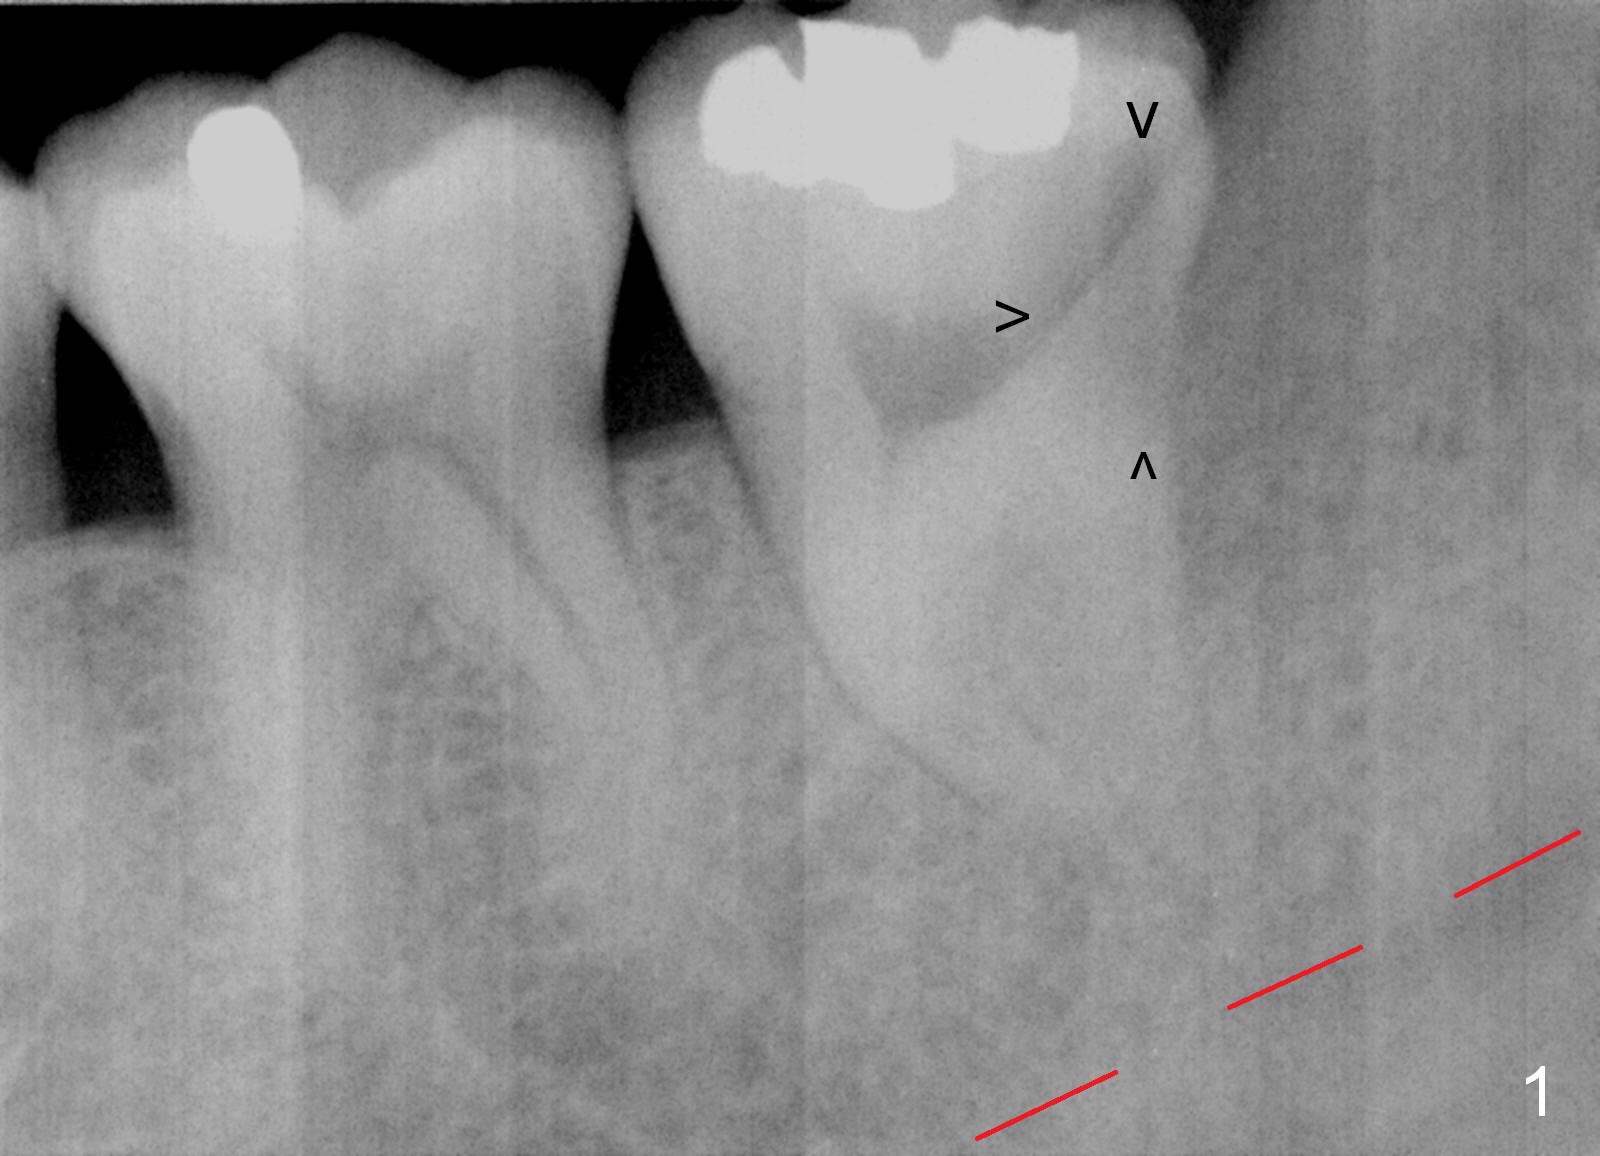

In fact, RCT is tried. Fourteen months later, the tooth remains symptomatic with mobility (Fig.6). Due to the distal defect caused by the 3rd molar (Fig.6,7 arrowheads), the implant should be placed as mesial and deep as possible.